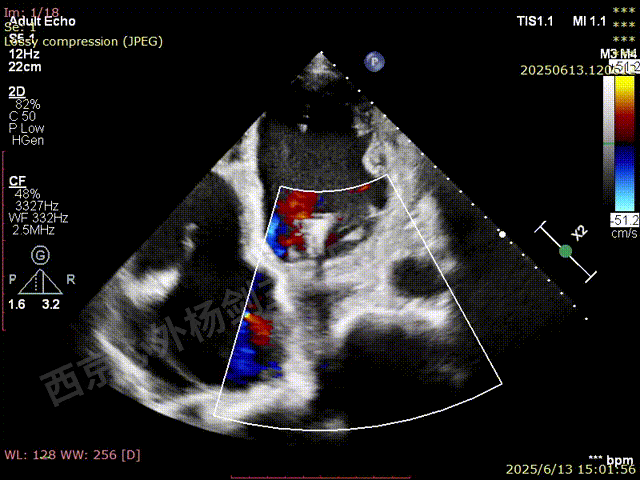

TAVR术后,全心增大,二尖瓣反流重度,三尖瓣反流重度。中量心包积液。左室严重增大,标准图像调整困难。主动脉瓣位带支架人工瓣膜瓣叶启闭正常,主动脉瓣位人工瓣上血流速度Vmax 148cm/s,PGmax 9mmHg,Vmean 86cm/s,PGmean 2mmHg, VTI 34.7cm,瓣周反流(轻)。估测肺动脉收缩压约49mmHg;左室收缩功能明显减低。LVEF:23%,EDV:364ml,ESV:221ml。

彩色血流示:二尖瓣反流缩流颈彩宽6.6mm,面积17cm²,容积30ml;二尖瓣瓣口面积6.6cm²,瓣环内径:左右径34mm,前后径34mm。2区瓣叶长度:前叶36mm,后叶20mm,叶环比1.6. 三尖反流面积17.2cm²,容积33ml,Vmax 291cm/s,PGmax 34mmHg。

二尖瓣后叶栓系严重,前叶相对错位,反流束沿2区分布广泛,2偏3区处存在反流。

反流宽度至少23mm,因影像调整困难,考虑实际反流更宽。